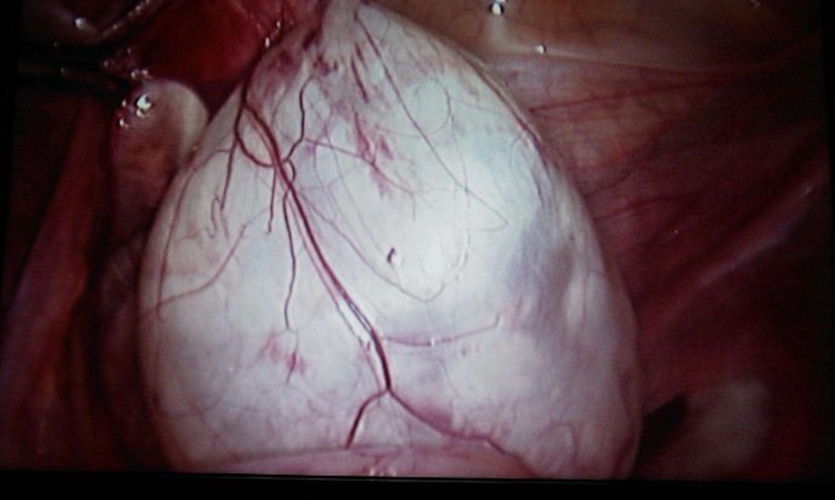

巧克力囊腫圖片

實拍巧克力囊腫

什麼是巧克力囊腫